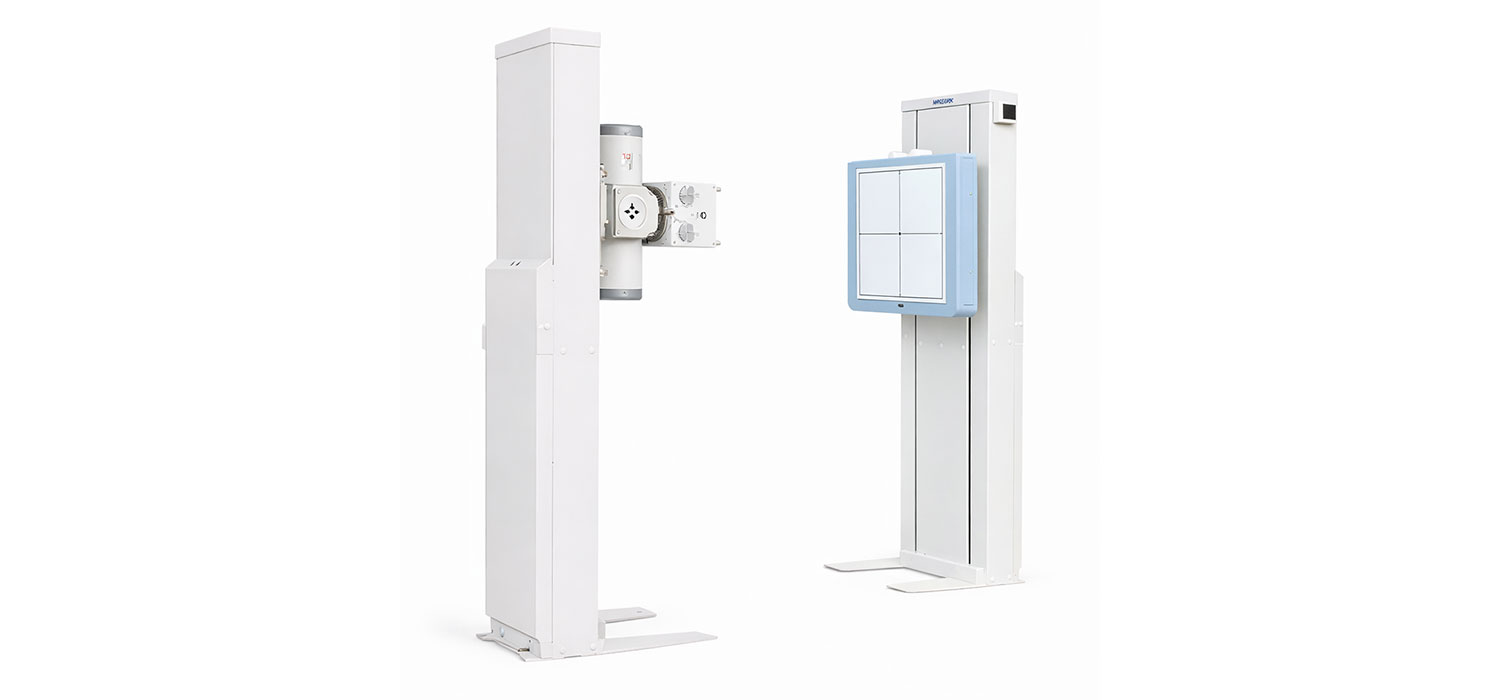

ELB System

ELB System is a compact digital radiography system with two synchronized stands, designed for examination-focused use.

Its light and thin structure allows easy installation, including use in medical examination vehicles.

Generator (inside)

Two-Stand Configuration

Two synchronized stands designed for examination-focused use.

Synchronized Stand Movement

Synchronized up-and-down movement for simple and efficient operation.

Light & Thin Design

Lightweight, slim structure suitable for easy installation and examination vehicles.

Compact Two-Stand Radiography System

ELB System is a compact digital radiography system composed of two synchronized stands, designed for examination-focused applications.

Two-Stand Radiography System

ELB System is a compact digital radiography system with two synchronized stands, designed for examination-focused imaging. It features synchronized vertical movement, adjustable SID, and a light, space-saving structure suitable for fixed and mobile installations.